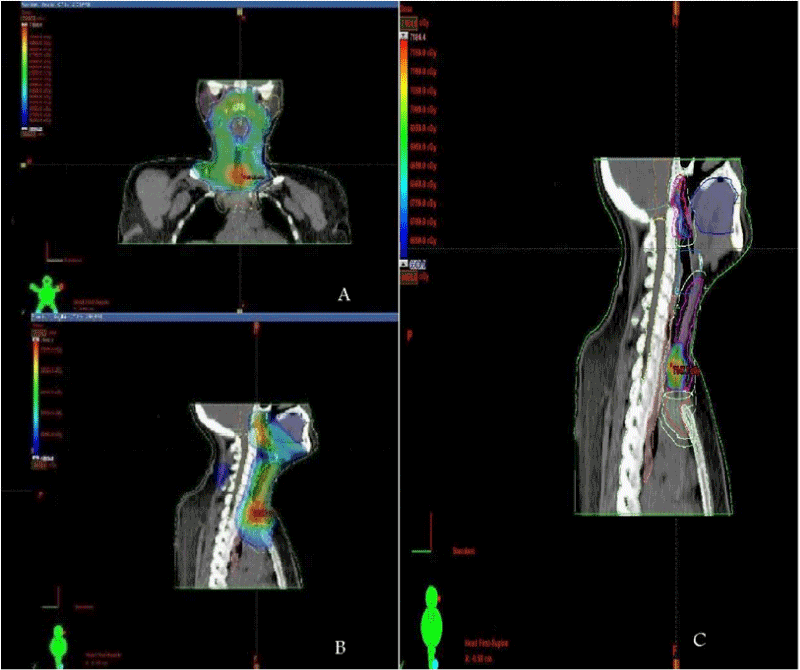

| Figure 1: Intensity modulated radiotherapy technique incorporated with 5-7 beamlets showing isodose distribution in axial, saggital and coronal images of phase 1 (A, B) and boost(C) in saggital and coronal views of MPR (multiplanar reconstructed radiographs). |